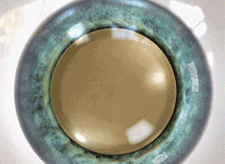

백내장수술 시 혼탁해진 수정체 대신 단초점 인공수정체 렌즈를 삽입했을 때와

다초점 인공수정체를 삽입했을 때의 시력 차이

정상안 / 정체가 혼탁해진 백내장 환자의 시야 / 백내장수술 시 단초점 인공수정체로 교체했을 때는 근거리 이용시 돋보기를 사용해야 합니다. / 백내장 수술 시 다초점 인공수정체로 교체했을 때 안경 없이 근거리에서 원거리까지 잘 볼 수 있습니다.